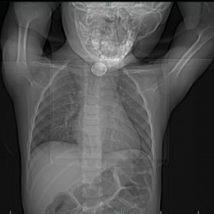

接诊医生第一时间为孩子完善检查,影像学结果让人心揪 —— 屏幕上清晰显示,一枚圆形异物牢牢卡在孩子喉间。更关键的是,这枚异物密度高,还出现了典型的 「双环征」,儿科医生凭借丰富经验判断:大概率是纽扣电池!

随后的胃镜检查证实了这一猜测:乐乐食管上段不仅卡着一枚纽扣电池,电池释放的有害物质已导致食道黏膜严重损伤,甚至有穿孔风险,情况十分危急。